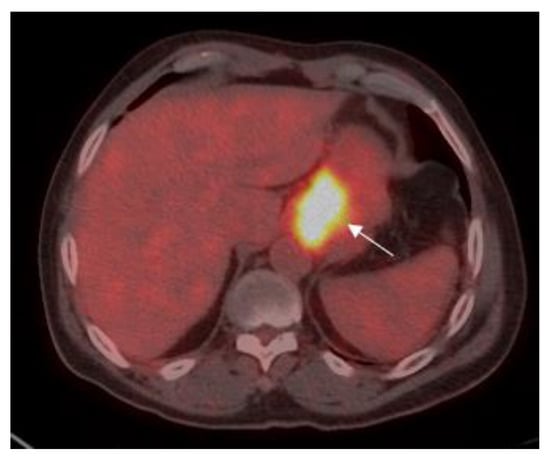

Patients were classified into two groups according to the level of SUV avidity of the primary lesion in the baseline PET-CT: the high-SUV (>3.5) group included 58 (52.3%) patients (Figure 1), and the low-SUV (≤3.5) group included 53 (47.7%) patients (Figure 2).

Figure 2. 75-year old male with gastric adenocarcinoma (SRCC). Axial PET-CT images show low 18F-FDG uptake (SUVmax: 3.5) in primary tumor in the body of the stomach (white arrow).